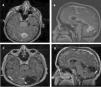

Intracranial hemangiopericytoma (HPC) is a rare central nervous system tumor characterized by its low incidence, high rate of local recurrence and risk of metastasis. The main objectives of this paper are two: to show the results in the treatment of HPC in our institution in the last 20 years and to make a review of the literature on this topic.

MethodsRetrospective review that includes patients diagnosed with intracranial solitary fibrous tumor/hemangiopericytoma (TFS/HPC) that have undergone surgery from 1997 to 2017. It includes patients that had nuclear expression of STAT6 (detected by immunohistochemistry) and grade II/III histopathological diagnosis (defined by the World Health Organization in 2016). We collected demographic data, tumor characteristics, treatment and survival of these patients.

ResultsA total of 19 patients fulfilled inclusion criteria. The median follow up was 96 months (12–230). The mortality rate was 21% (n = 4). The median follow up survival was 19.16 years. 57.9% of patients presented at least 1 tumor recurrence (n = 11) (recurrences of 6%, 67% y 90% at 1, 5 and 10 years). Five patients presented extracranial metastasis. Patients with tumors <6 cm had greater survival (p < 0.05).